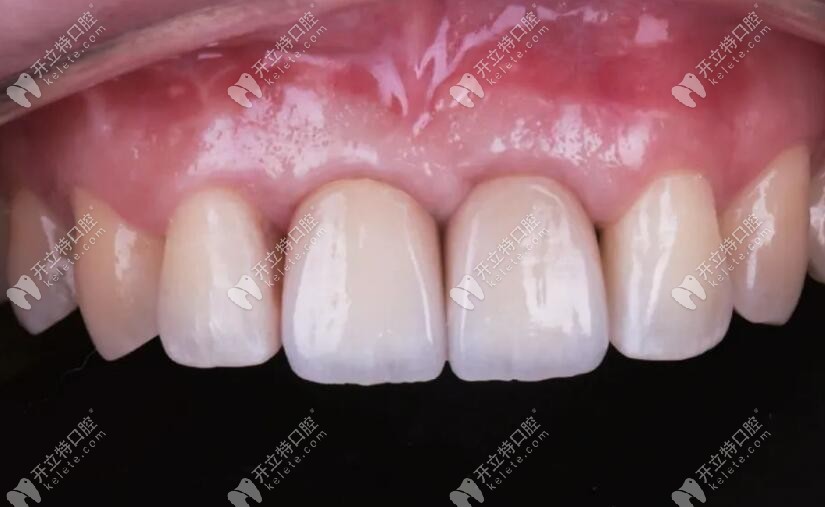

兩顆前牙冠材料的選擇是:愛爾創(chuàng)瓷倍健全瓷牙

1、材料顏色層次從頸部到切緣的逐步過度,接近自然牙齒。

2、透亮也可以達(dá)到前牙美觀上的要求。